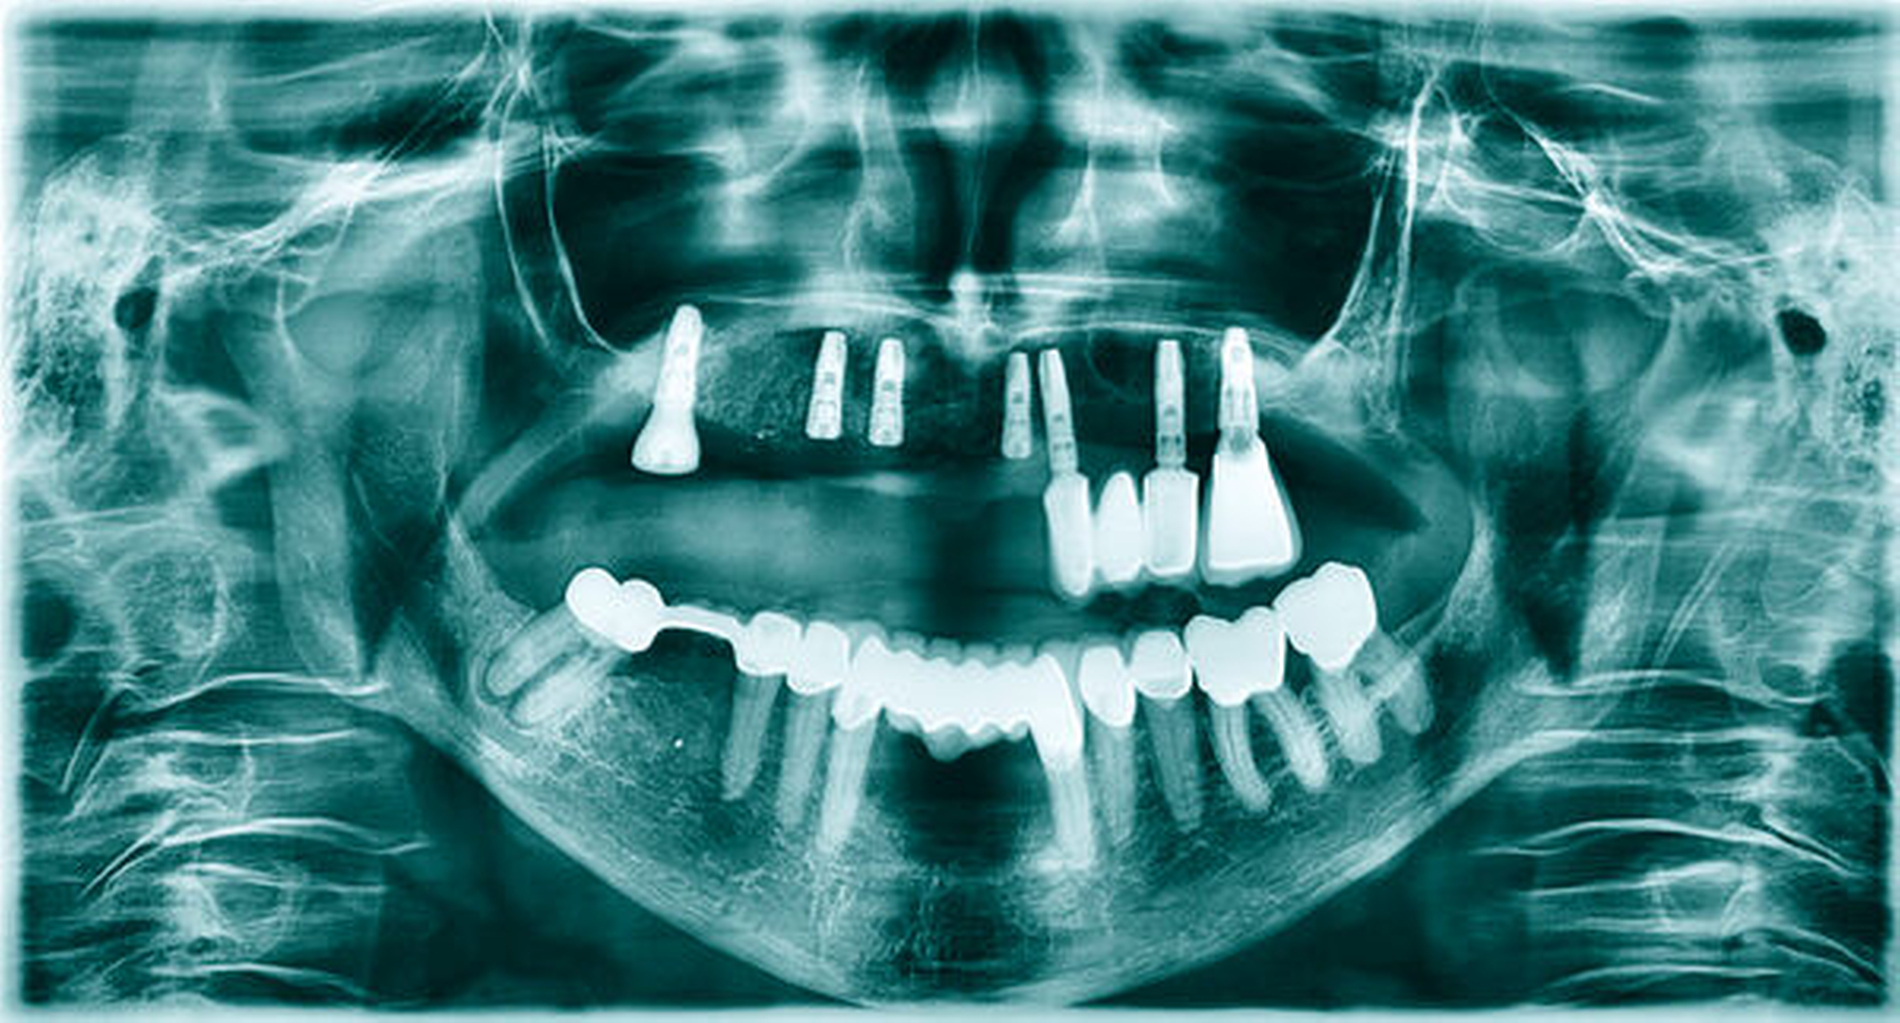

Drei Monate nach Augmentation wurden drei Astra-Tech-EV-Implantate in regio 13, 12 und 22 (jeweils Durchmesser 4,2 mm, Länge 11 mm) nach Entfernung der Osteosyntheseschrauben inseriert sowie das Implantat in regio 16 freigelegt (Abbildung 8). Es zeigten sich dabei stabile knöcherne Verhältnisse mit einer guten Revaskularisation des augmentierten Bereichs. Der Wundverschluss erfolgte analog zu dem bei der Augmentation. Auch hier ergab sich eine ereignislose Wundheilung, so dass die Implantate in regio 13, 12 und 22 nach weiteren drei Monaten freigelegt werden konnten (Abbildung 9). Aufgrund des abgeflachten Vestibulums und der geringen Breite der vestibulären keratinisierten Gingiva erfolgte eine Vestibulumplastik in Kombination mit freien Schleimhauttransplantaten (Abbildung 10).